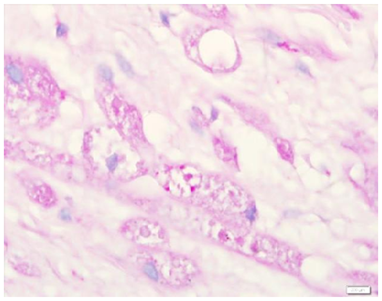

An excision biopsy specimen from a mass at elbow of 26 years old female patient was received for histopathological examination. The clinical impression was of ‘benign soft tissue tumor’. The specimen was received in 10% formalin in one container. On gross examination, it was a 1.5 x 1 x 0.5 cm well-circumscribed, grey-tan mass, without skin component. The cut surface was solid homogenous and no necrotic or hemorrhagic areas were found on it. The microscopic examination revealed a circumscribed encapsulated lesion composed of round to polygonal to spindle shaped cells with eosinophilic granular cytoplasm and centrally placed small nuclei (Figure 1 & Figure 2). Cells were arranged in intersecting bundles and mixed with fibrous connective tissue (Figure 3). The Intralesional peripheral nerve bundles surrounded by the lesional cells were seen (Figure 4). No significant mitoses or cells with cross striation, significant inflammatory infiltrate or necrosis were seen. IHC showed positive results for S100 (Figure 5) and neuron-specific Enolase (NSE) (Figure 6). Smooth muscle actin (SMA) (Figure 7) and Myogenin were negative. CEA was focally positive. Periodic acid-schiff (PAS) stain showed PAS positive intracytoplasmic granules (Figure 8). The lesion was completely excised with <1mm safety margin. Focal entrapment of the adjacent fatty tissue was observed. Based on the above mentioned findings, diagnosis of granular cell tumor (GCT) was made.

Figure 1 & 2 circumscribed encapsulated lesion composed of round to polygonal to spindle shaped cells with eosinophilic granular cytoplasm and centrally placed small nuclei.